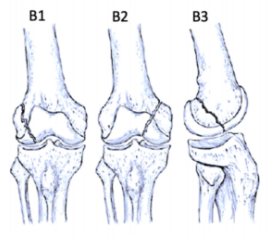

股骨远端骨折可根据骨折模式、部位和膝关节受累情况进行分型 ,AO/OTA分型常用于对这些骨折进行分类。在每个类别中,骨折可根据复杂性和移位程度进一步分类,对于与全膝关节置换术(TKA)相关的假体周围股骨远端骨折,基于骨折移位和TKA股骨假体完整性的Lewis和Rorabeck分型(1997年)是最常用的分型:

A型:关节外骨折

不累及关节面

B型:部分关节内骨折

累及部分关节面但保持一定的关节匹配性

C型:完全关节内骨折

关节面完全破坏